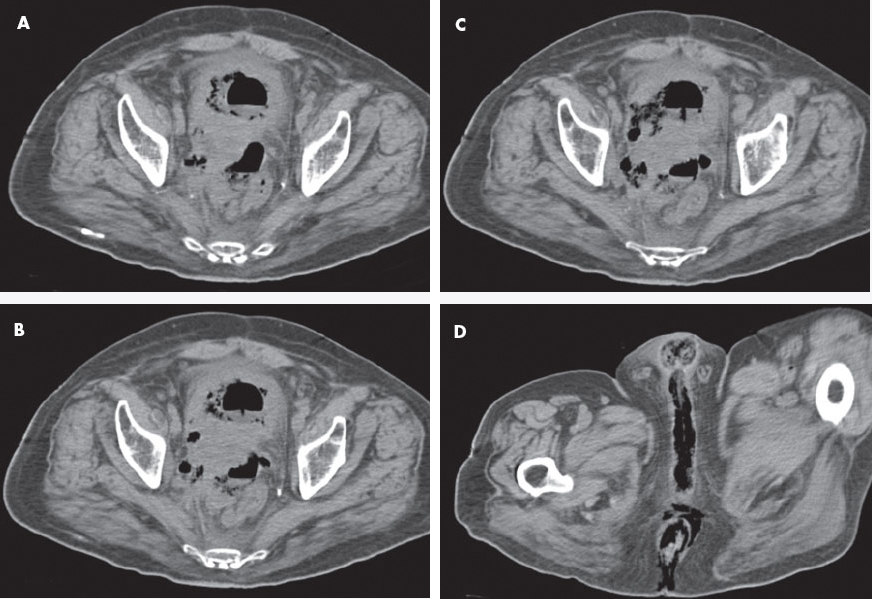

CT scans of the abdomen and pelvis showed a large prostatic mass without delineation between the prostate, rectum, and bladder. A fistula was noted between the rectum and bladder (A, B, and C). Copious subcutaneous gas was visible in the perineum and in all 3 corpora of the penis (D). Blood cultures were positive for Clostridium perfringens. Necrotizing fasciitis was diagnosed, and the patient underwent a loop colostomy.